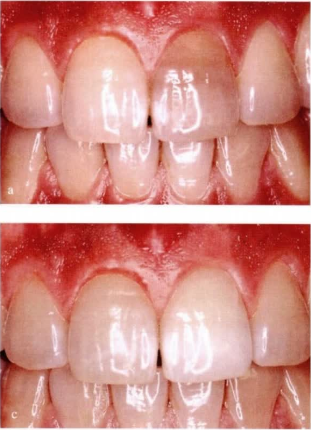

有些人因為死髓牙影響美觀而找牙醫處理,這種情況很多時候會建議先做內漂白後再做個冠修復,那麼死髓牙該怎麼漂白呢?

1、顏色評估:術前照相記錄漂白前的顏色,為漂白後顏色對比提供參考。

4、暫封材料封閉:為了嚴密封閉,暫封材料最小厚度應為 2mm。由於漂白材料會釋放O·,產生的壓力可能使暫封材料被頂脫。為防止此類情況發生,可以用玻璃離子作為暫封材料。6、顏色評估:3~5天後約患者復查,並與鄰牙顏色進行對比。如果漂白發生過快,可要求患者提早復查。視病因和變色程度的不同,漂白過程通常需重複3~5次,直到患牙顏色較稍亮時為止。這種“過漂白”可為患牙在顏色穩定後的顏色反彈提供一些補償。